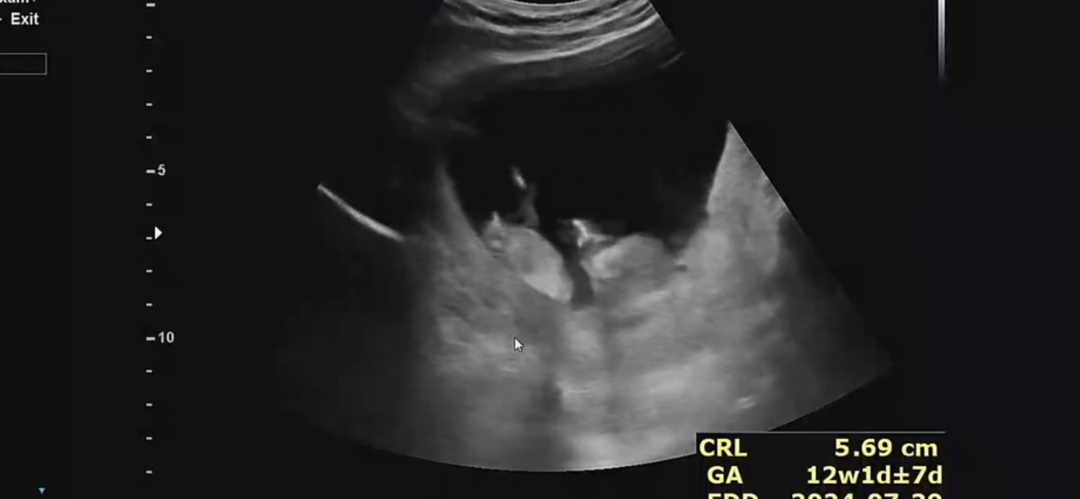

흐리지만 아들같아용ㅎ

고수님들👍🏻 12주차입니당ㅋㅋ 성별이 너무 궁금해서 오늘 잠못잘것 같아요ㅠㅠ 각도법 제발 의견 좀 부탁드려용🙏🏻